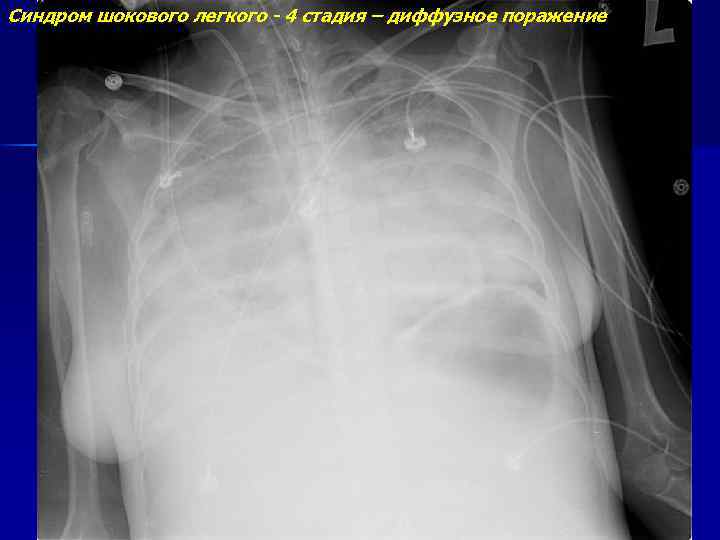

Синдром шокового легкого - 4 стадия – диффузное поражение